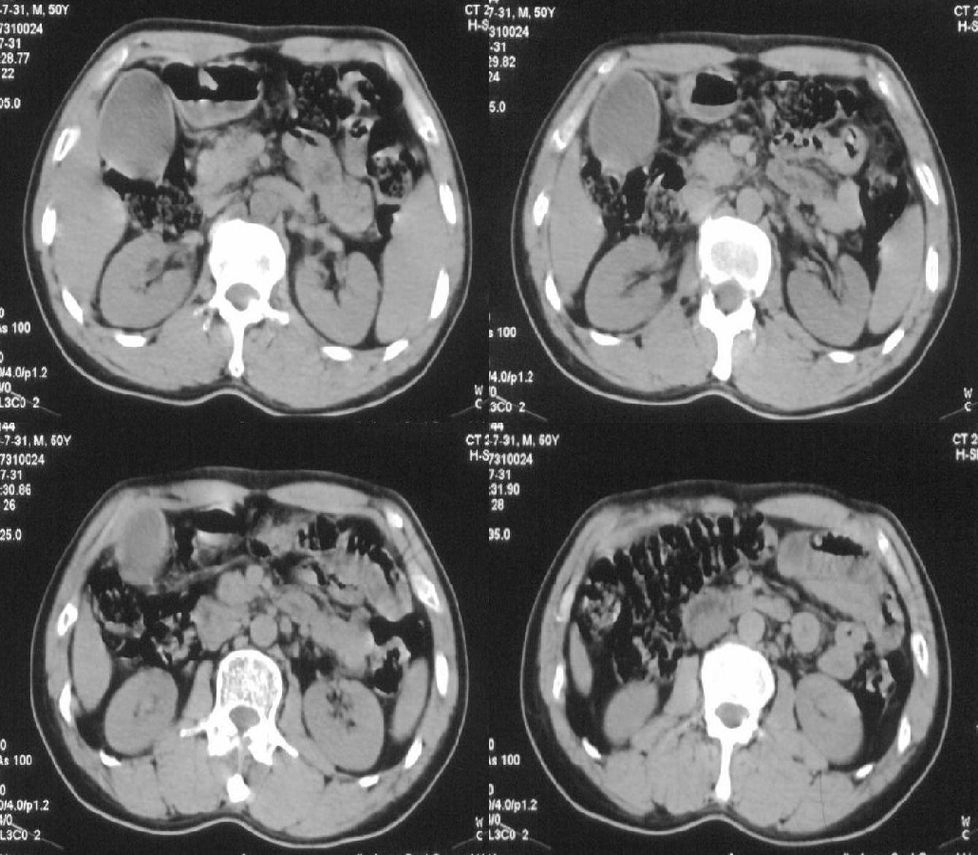

标题: CT21384:男性,50岁。发现无痛性黄疸十余天,B朝提示肝胆管 [打印本页]

标题: CT21384:男性,50岁。发现无痛性黄疸十余天,B朝提示肝胆管

1.考虑:壶腹占位病变(癌?)。

2.胆系低位梗阻:肝内外胆管扩张,胆囊增大,胰管扩张。

胰头癌伴低位胆道梗阻。

胆系低位梗阻(肝内外胆管扩张,胆囊增大,胰管扩张);考虑胰头癌或壶腹癌所致。

胆总管突然中断,壁增厚且强化,考虑胆总管癌可能性大伴胆系梗阻,胆囊炎

胰头强化欠均匀,胆胰管扩张。考虑胰头癌可能性大。

胆系低位梗阻(肝内外胆管扩张,胆囊增大,胰管扩张,钩突似有占位);考虑胰头癌